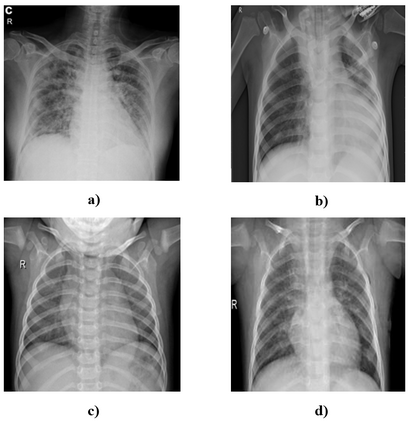

The new coronavirus 2019, also known as COVID19, is a very serious epidemic that has killed thousands or even millions of people since December 2019. It was defined as a pandemic by the world health organization in March 2020. It is stated that this virus is usually transmitted by droplets caused by sneezing or coughing, or by touching infected surfaces. The presence of the virus is detected by real-time reverse transcriptase polymerase chain reaction (rRT-PCR) tests with the help of a swab taken from the nose or throat. In addition, X-ray and CT imaging methods are also used to support this method. Since it is known that the accuracy sensitivity in rRT-PCR test is low, auxiliary diagnostic methods have a very important place. Computer-aided diagnosis and detection systems are developed especially with the help of X-ray and CT images. Studies on the detection of COVID19 in the literature are increasing day by day. In this study, the effect of different batch size (BH=3, 10, 20, 30, 40, and 50) parameter values on their performance in detecting COVID19 and other classes was investigated using data belonging to 4 different (Viral Pneumonia, COVID19, Normal, Bacterial Pneumonia) classes. The study was carried out using a pre-trained ResNet50 convolutional neural network. According to the obtained results, they performed closely on the training and test data. However, it was observed that the steady state in the test data was delayed as the batch size value increased. The highest COVID19 detection was 95.17% for BH = 3, while the overall accuracy value was 97.97% with BH = 20. According to the findings, it can be said that the batch size value does not affect the overall performance significantly, but the increase in the batch size value delays obtaining stable results.